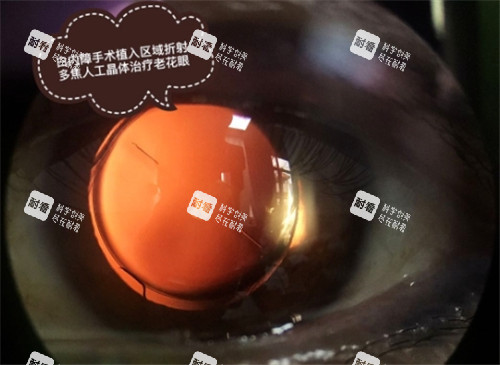

白内障手术费用区间:单侧白内障超声乳化摘除术+人工晶体植入术:3000元-8000元;双侧白内障超声乳化摘除术+人工晶体植入术:5000元-15000元;使用进口折叠晶体或非球面晶体的手术费用会相应提高。